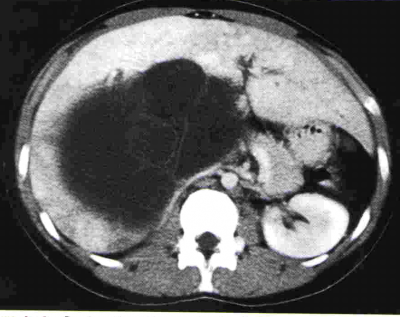

בטומוגרפיה ממוחשבת ניתן לראות מילוי של חומר ניגוד בהמנגיומה (תצלומים 15.10-17.10).

| תצלום 25.10: ציסטות מרובות בכבד. מימין הציסטות הן חלק ממחלה פוליציסטית מערכתית. משמאל ציסטות המוגבלות לכבד בלבד. | |